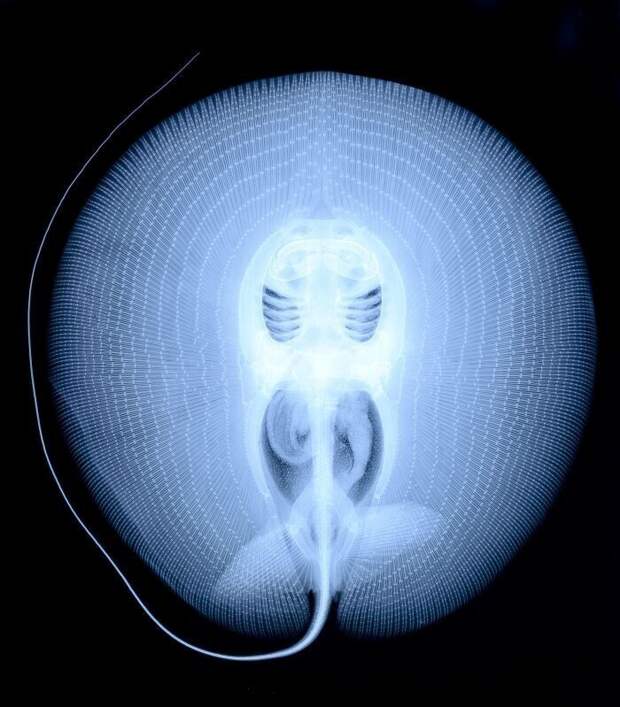

Рентгеновский снимок ската-хвостокола